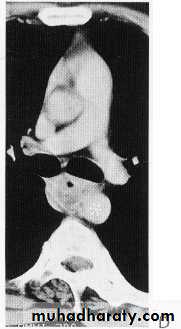

Ca ESOPH.

Ct scan carinal LAP